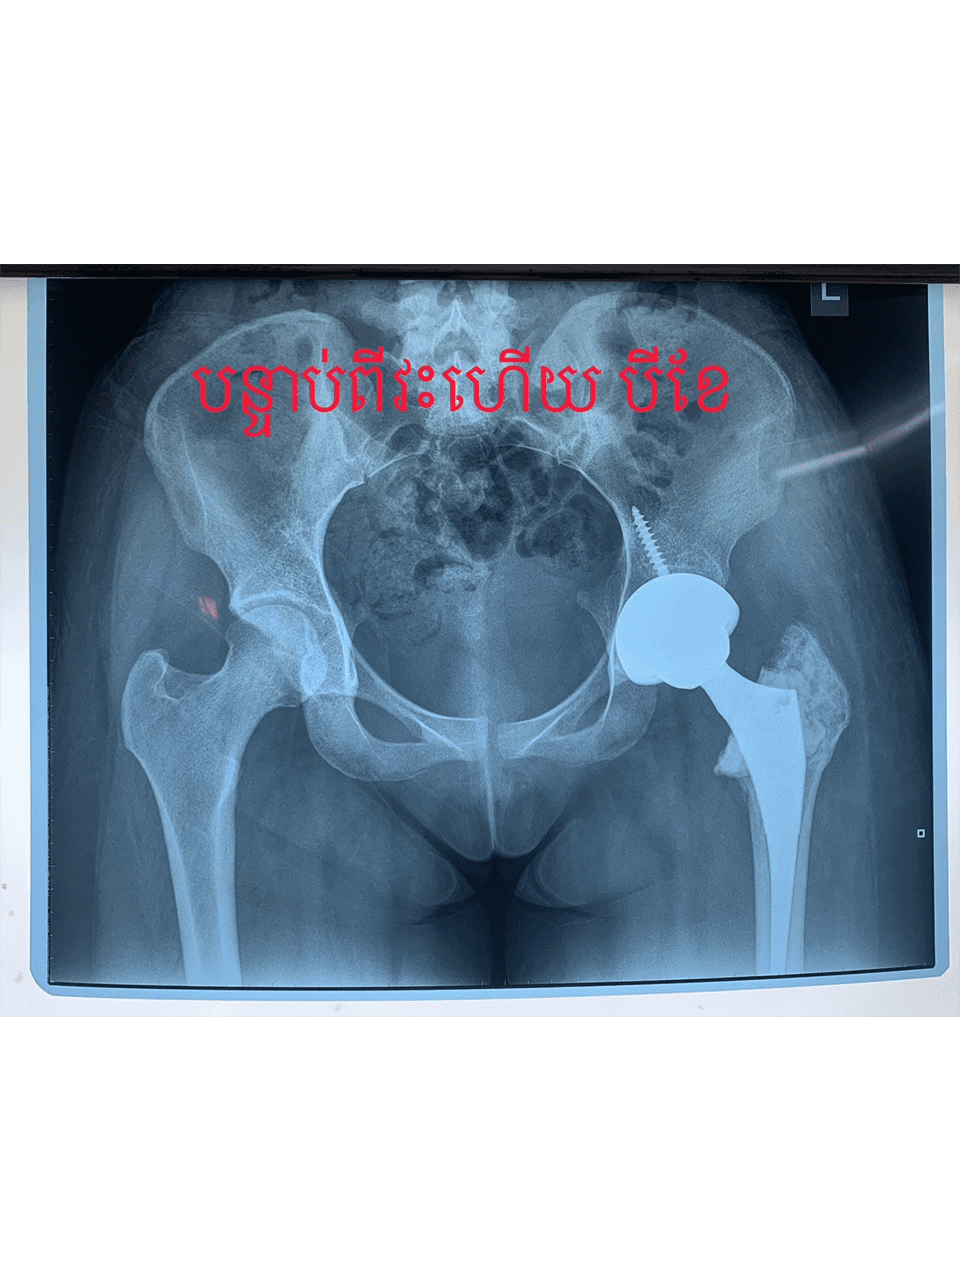

Dr. Weber and his partners participate in short term medical mission trips to Cambodia. Dr. Weber has had the pleasure of going twice now in 2018 and 2020. During these trips Dr. Weber performs total hip replacements on patients who normally would have no treatment options. To learn more and to see videos from the experience please click the links below.